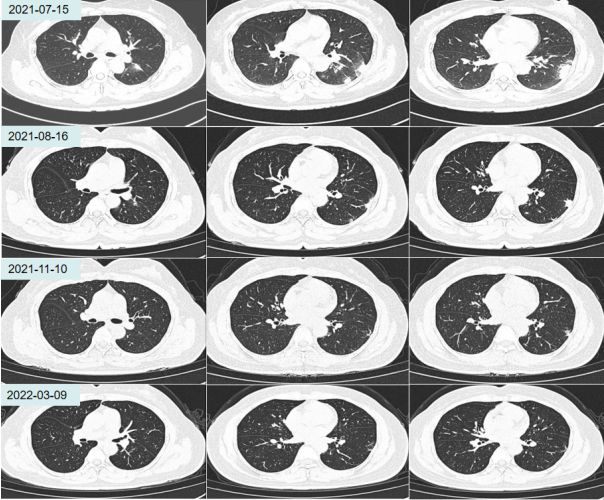

2017年8月患者出现面部扁平红斑,分布于脸颊及鼻梁,伴双侧腕关节及踝关节间断性疼痛和明显脱发,并出现双侧手掌及指尖皮下红色硬结。至深圳市A医院皮肤科门诊完善检查(具体不详),诊断为“结缔组织病”,建议住院进一步诊治,家属拒绝,并自行给患者服用中药(不详)。用药后患者面部红斑及皮下红色硬结可消退,脱发症状减轻。